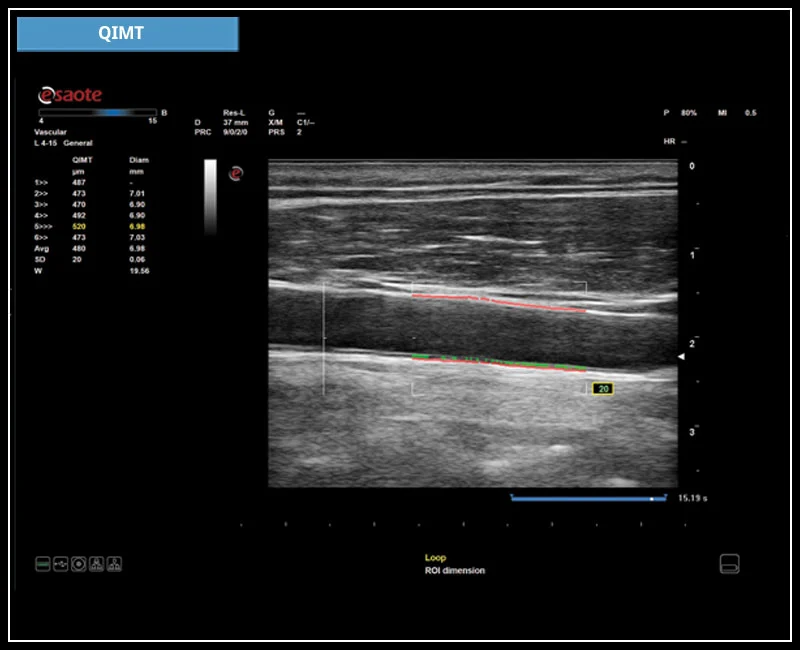

MyLab™9 Platform - QIMT Intima-media thickness quantification based on radio frequencies in real-time studies

MyLab™9 Platform - QIMT Intima-media thickness quantification based on radio frequencies in real-time studies

MyLab™X1 - Carotid IMT Calculation

MyLab™X1 - Carotid IMT Calculation

MyLab™X8 Platform - Real-time measurement of the Intima Media with QIMT

MyLab™X8 Platform - Real-time measurement of the Intima Media with QIMT

MyLab™X5 - QIMT

MyLab™X5 - QIMT

MyLab™X6 - QIMT

MyLab™X6 - QIMT

MyLab™X7 - QIMT

MyLab™X7 - QIMT

MyLab™Omega - RF QIMT

MyLab™Omega - RF QIMT